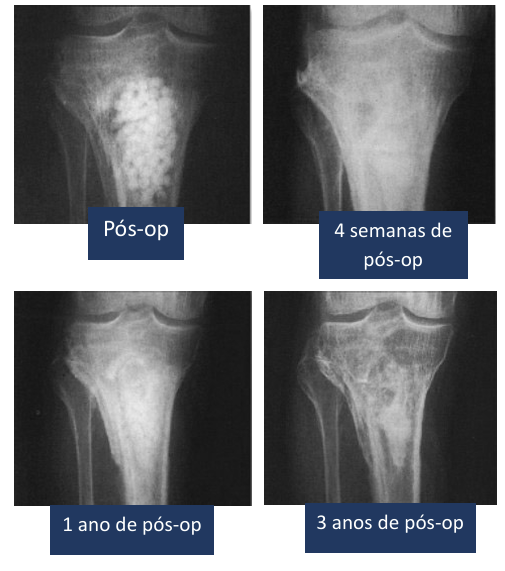

Relatos de Caso

Casos clínicos que demonstram resultados

Depoimentos

Os resultados preliminares mostraram-se muito satisfatórios com o uso do PerOssal como substituto ósseo em falhas previamente infectadas, ou mesmo naquelas com elevado potencial para infecção. Ele une a possibilidade de associar antibiótico, para uma ação bactericida local, com a nano hidroxiapatita, eficaz como osteocondutor, que leva maior chance de consolidação da lesão.